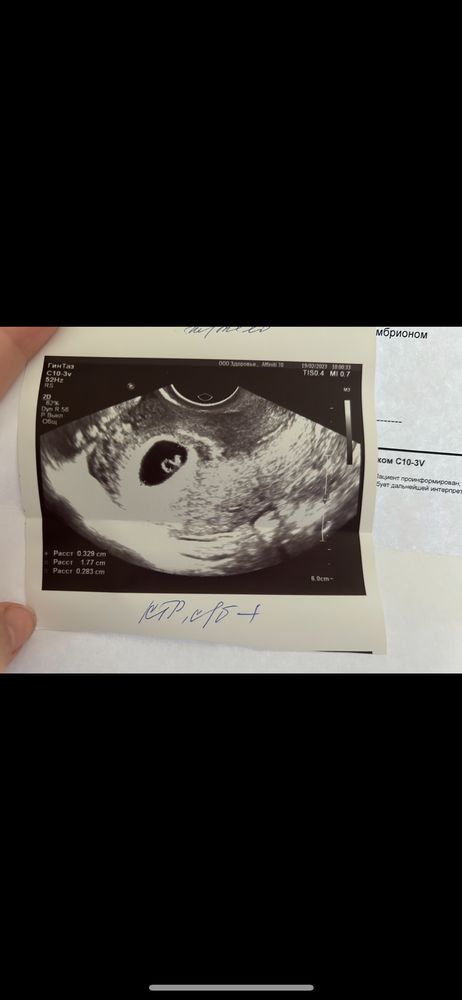

Изображение Кристина,

Кристина, место прикрепления,выражено белым справа.